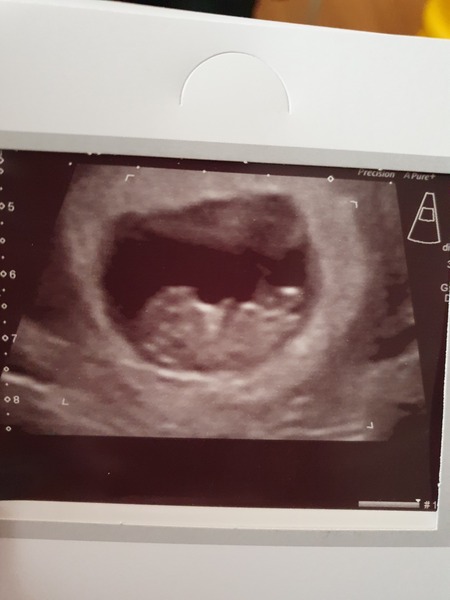

All has gone as well as we could have hoped so far. Measuring exactly on my dates at 9+3. Baby was wriggling away 😍

Lovely pic @Treaclepie19 glad all is well for you!!

Thank you Smile It's made it all a bit more real seeing those little legs kicking about.